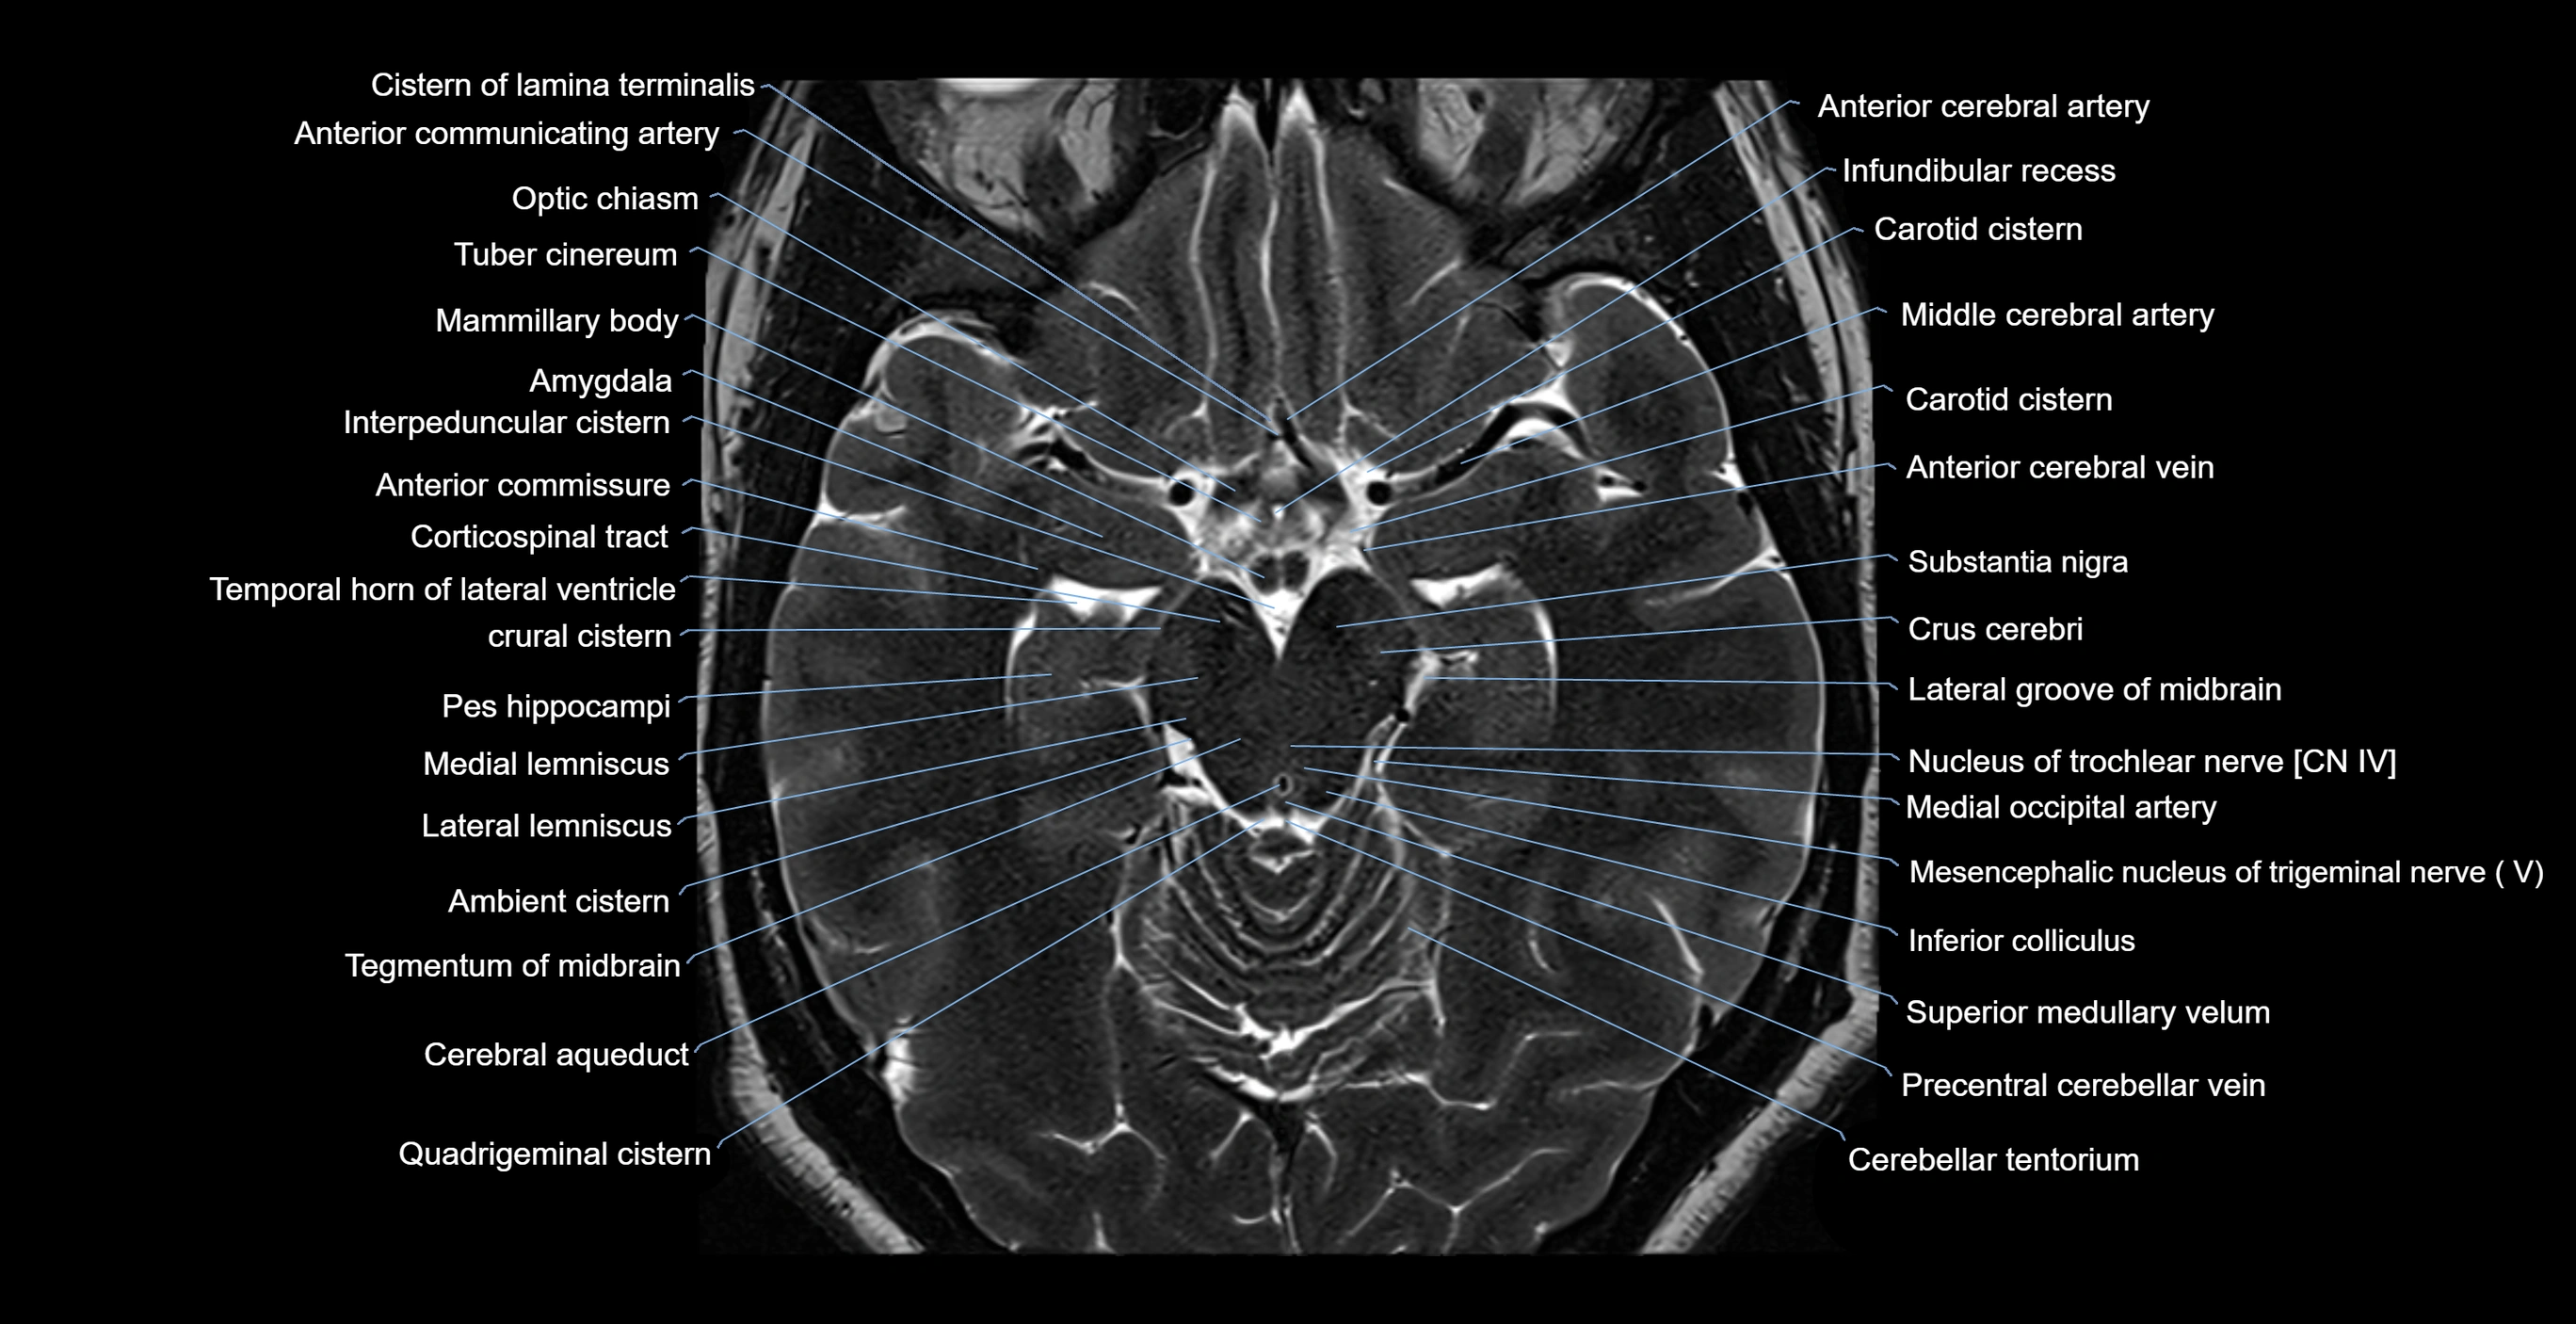

- Ambient cistern

- Amygdala

- Anterior Communicating Artery

- Anterior cerebral artery

- Anterior commissure

- Carotid cistern

- Cerebral aqueduct

- Cerebral crus

- Cistern of lamina terminalis

- Corticospinal tract

- Crural cistern

- Crus cerebri

- Inferior colliculus

- Interpeduncular Cistern

- Lateral lemniscus

- Mammillary body

- Medial lemniscus

- Medial occipital artery

- Mesencephalic nucleus of trigeminal nerve

- Middle cerebral artery

- Nucleus of oculomotor nerve

- Nucleus of trochlear nerve

- Optic chiasm

- Posterior cerebral artery

- Substantia nigra

- Tegmentum of midbrain

- Temporal horn of lateral ventricle

- Tuber cinereum